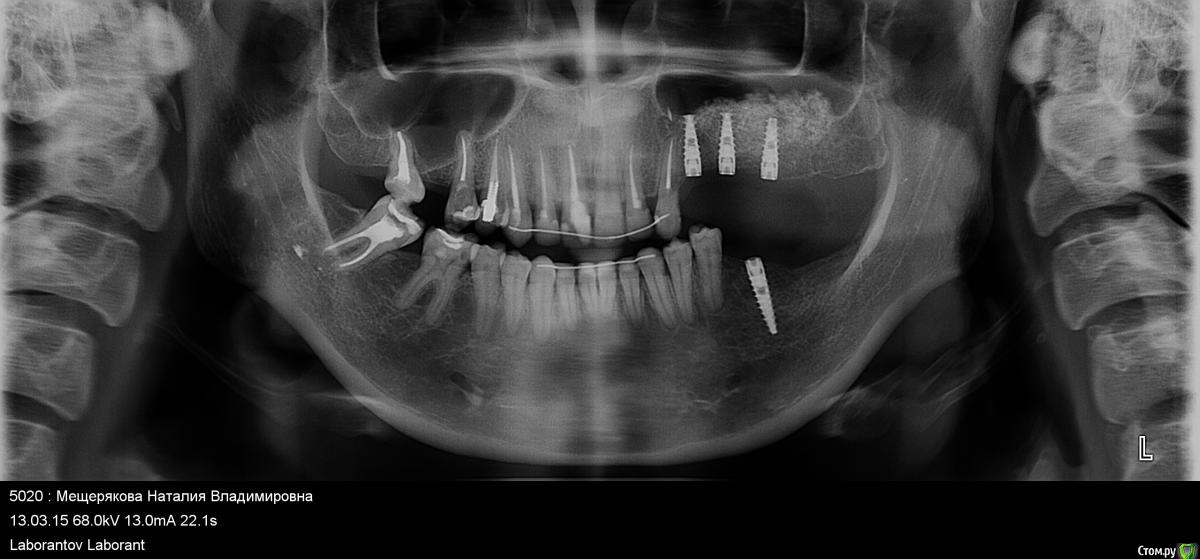

Arzella Опубликовано 2 мая, 2015 Автор Поделиться Опубликовано 2 мая, 2015 Не нравится, что коронки стоят выше уровня своих зубов. Еще напрягает, что имплант как-то уж совсем близко к клыку стоит. Ссылка на комментарий

doca Опубликовано 3 мая, 2015 Поделиться Опубликовано 3 мая, 2015 Не нравится, что коронки стоят выше уровня своих зубов. Еще напрягает, что имплант как-то уж совсем близко к клыку стоит.Имплант стоит к клыку абсолютно нормально,часто на таких снимках имплант вообще накладывается на корень зуба 3 Ссылка на комментарий